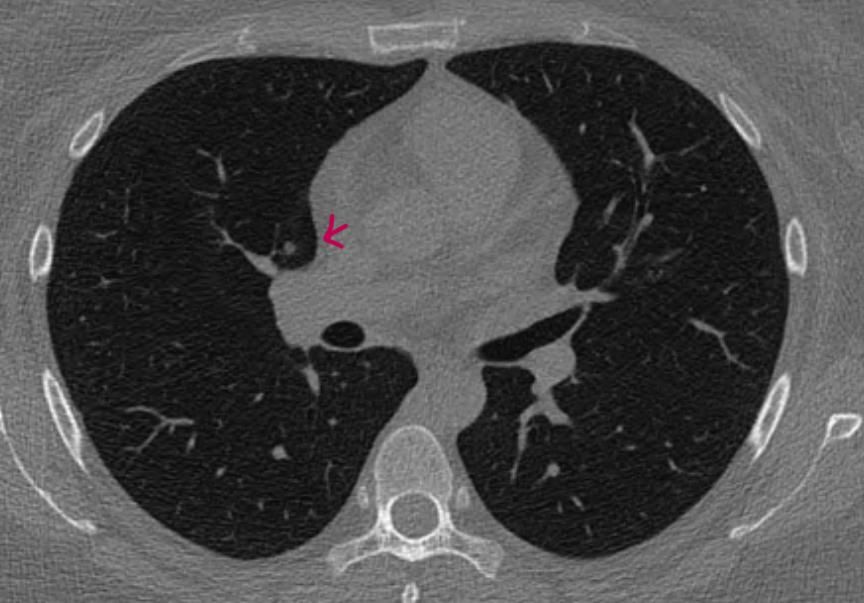

일단은 첫번째 영상은 크기가 애매해서 말씀드리기는 어려운 것 같구요

둘째 영상과 셋째 영상은 둘다 간유리음영으로 보셔도 될 것 같습니다.

물론 둘째 영상보다 셋째 영상이 더욱 흐지부지하게 보이기는 하지만

그렇다고 둘째 영상이 고형성이라고 보기는 어려울 것 같습니다.